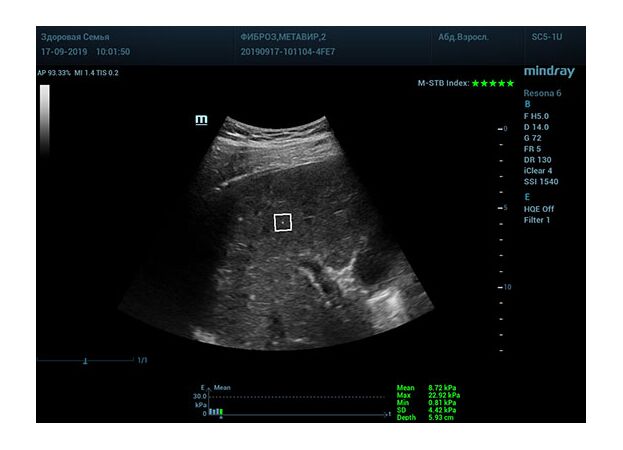

Определение плотности печени. Не ошибся ли оператор при измерении эластических свойств печени? Для оценки критериев качества предусмотрен индекс MBT, который покажет насколько «твердой» была рука оператора и двигалась ли печень. При MBT 5* рука тверда и показатели достоверны. Для оценки качества результатов используется IQR индекс, отображающий колебания показателей в точке измерения при расчете медианы. Показатели при IQR <30% считаются приемлемыми. Техника сканирования через межреберные промежутки требует размещение окна интереса на несколько сантиметром ниже капсулы, для исключения эффекта реверберации. Установка ROI на паренхиму без захвата сосудов, для исключения погрешностей измерения.

Стадия фиброза определяется по системе METAVIR Staging, построенной на данных биопсии и сопоставлении с данными эластографии. Своевременная диагностика фиброза, и начало его лечения, залог благоприятного исхода заболевания.

• METAVIRF0 – норма.

• METAVIRF1 – Портальный фиброз без вовлечения перегородок

• METAVIRF2 – Портальный фиброз с вовлечением нескольких перегородок

• METAVIRF3 – Портальный фиброз с вовлечением множества перегородок

• METAVIRF4 – Цирроз.